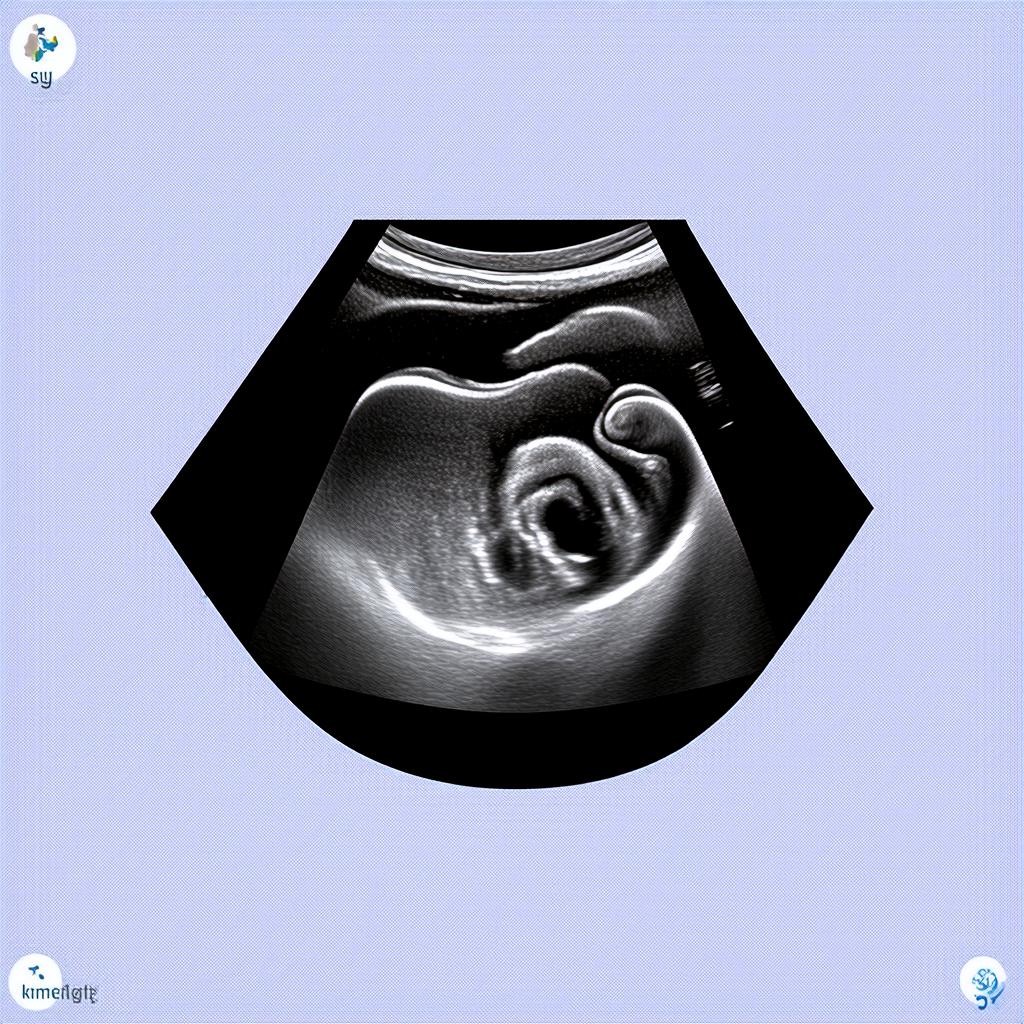

Определение пола ребенка на УЗИ в 20 недель: девочка

20 недель беременности — это важный этап, когда будущие родители могут узнать пол своего малыша. Ультразвуковое исследование (УЗИ) на этом сроке является частью второго скрининга и позволяет не только определить пол ребенка, но и оценить его развитие. Если врач сообщает, что у вас будет девочка, это повод для радости и подготовки к рождению малышки.

УЗИ на 20 неделе беременности проводится трансабдоминально, то есть через живот. Процедура безопасна для матери и ребенка и занимает около 20-30 минут. Врач оценивает:

- Размеры плода (фетометрия)

- Состояние плаценты и околоплодных вод

- Работу сердца и других органов

- Половые признаки для определения пола